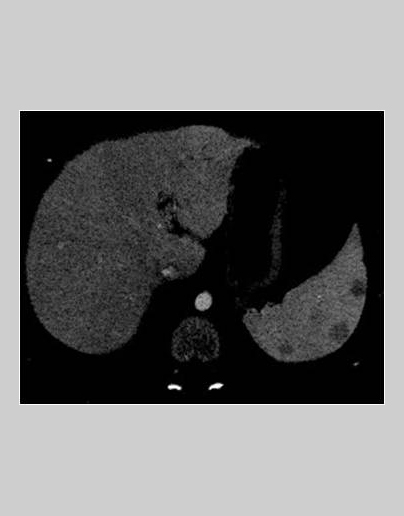

Se aprecian cuatro lesiones hipodensas en el bazo. En los cortes coronales se aprecia hipercaptación mucosa en las asas del yeyuno, adenopatías de tamaño patológico, aumento de la vascularización del meso y líquido libre en la fosa iliaca derecha.

• Hígado homogéneo sin lesiones focales. No hay dilatación de vía biliar. Riñones de tamaño, morfología y densidad normales, sin dilatación de vía urinaria. Páncreas, suprarrenales y vejiga normales.

• Se observan al menos cuatro lesiones focales esplénicas, hipodensas y mal definidas, con bazo de tamaño normal.